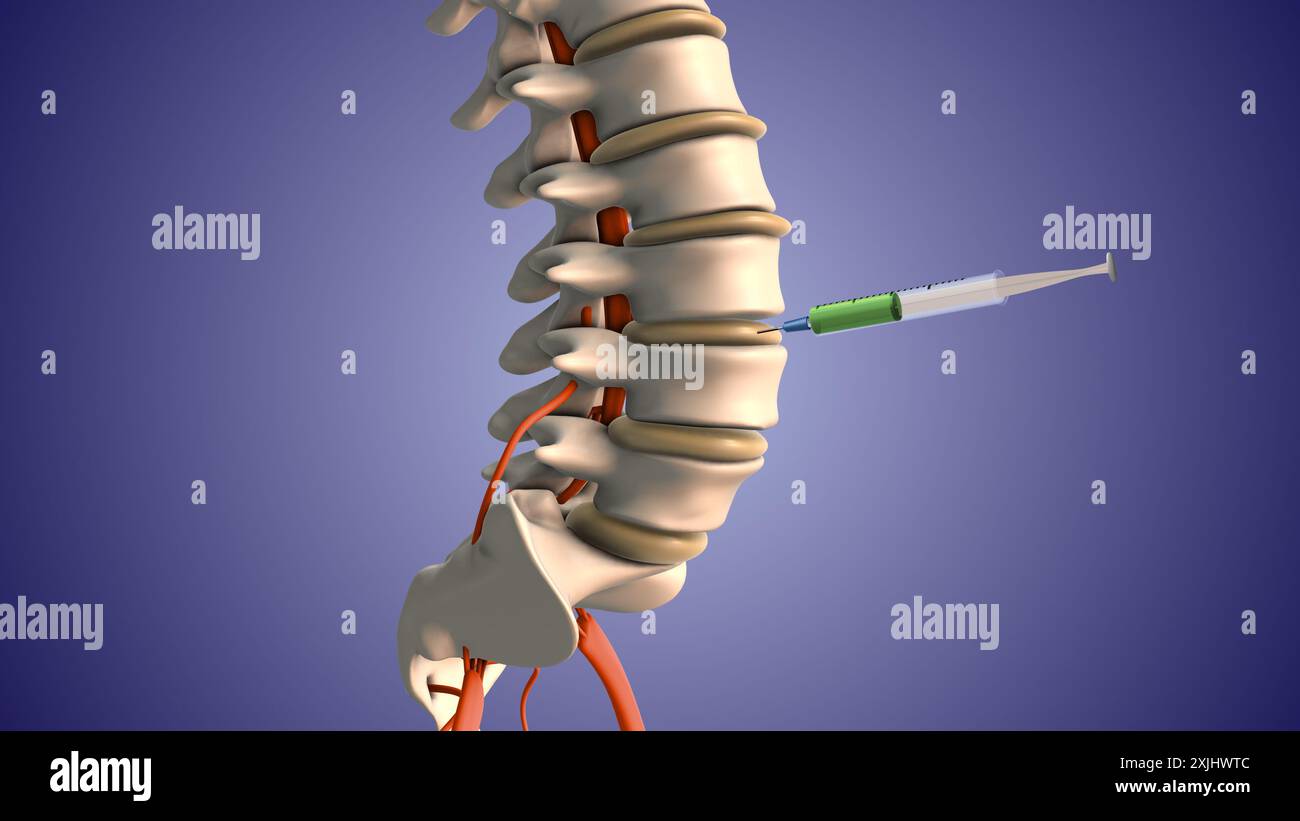

Injektion von Steroiden zur Behandlung von Bandscheibenvorfällen Stockfotohttps://www.alamy.de/image-license-details/?v=1https://www.alamy.de/injektion-von-steroiden-zur-behandlung-von-bandscheibenvorfallen-image613820155.html

Injektion von Steroiden zur Behandlung von Bandscheibenvorfällen Stockfotohttps://www.alamy.de/image-license-details/?v=1https://www.alamy.de/injektion-von-steroiden-zur-behandlung-von-bandscheibenvorfallen-image613820155.htmlRF2XJHWTB–Injektion von Steroiden zur Behandlung von Bandscheibenvorfällen

Injektion von Steroiden zur Behandlung von Bandscheibenvorfällen Stockfotohttps://www.alamy.de/image-license-details/?v=1https://www.alamy.de/injektion-von-steroiden-zur-behandlung-von-bandscheibenvorfallen-image613820158.html

Injektion von Steroiden zur Behandlung von Bandscheibenvorfällen Stockfotohttps://www.alamy.de/image-license-details/?v=1https://www.alamy.de/injektion-von-steroiden-zur-behandlung-von-bandscheibenvorfallen-image613820158.htmlRF2XJHWTE–Injektion von Steroiden zur Behandlung von Bandscheibenvorfällen

Injektion von Steroiden zur Behandlung von Bandscheibenvorfällen Stockfotohttps://www.alamy.de/image-license-details/?v=1https://www.alamy.de/injektion-von-steroiden-zur-behandlung-von-bandscheibenvorfallen-image613820156.html

Injektion von Steroiden zur Behandlung von Bandscheibenvorfällen Stockfotohttps://www.alamy.de/image-license-details/?v=1https://www.alamy.de/injektion-von-steroiden-zur-behandlung-von-bandscheibenvorfallen-image613820156.htmlRF2XJHWTC–Injektion von Steroiden zur Behandlung von Bandscheibenvorfällen

Injektion von Steroiden zur Behandlung von Bandscheibenvorfällen Stockfotohttps://www.alamy.de/image-license-details/?v=1https://www.alamy.de/injektion-von-steroiden-zur-behandlung-von-bandscheibenvorfallen-image613820157.html

Injektion von Steroiden zur Behandlung von Bandscheibenvorfällen Stockfotohttps://www.alamy.de/image-license-details/?v=1https://www.alamy.de/injektion-von-steroiden-zur-behandlung-von-bandscheibenvorfallen-image613820157.htmlRF2XJHWTD–Injektion von Steroiden zur Behandlung von Bandscheibenvorfällen